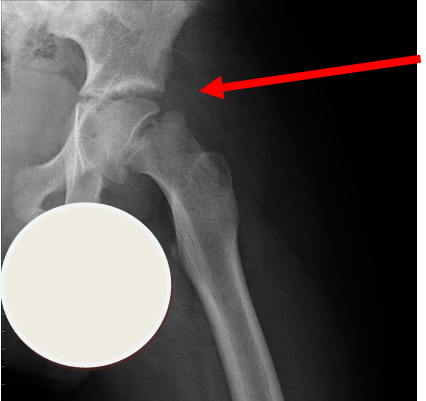

3.Perthes Disease

Case courtesy of A.Prof Frank Gaillard, Radiopaedia.org. From the case rID: 7980

Perthes disease or avascular necrosis of the capital femoral epiphysis is more common in boys than girls (approximately 4:1).  Onset is usually over weeks and typically between the ages of  3-9 years old.  15% are bilateral.  X-ray of the pelvis shows flattening of the femoral head with joint space widening.  X-ray changes may be absent in early disease.

The child is systemically well with no other joint involvement and no evidence of joint inflammation.

Investigation

• X-ray - AP pelvis